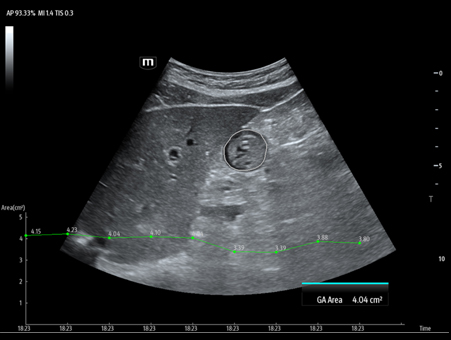

Reimagined safety and adaptability

MindrayŌĆÖs Anesthesia Ultrasound solutions address your biggest perioperative challenges such as treatment efficacy and patient safety, to improve patient outcomes in the operating room. We recognize the human side of healthcare and your role in providing best-in-class patient care, which is why we designed products suited to your clinical needs in this environment.